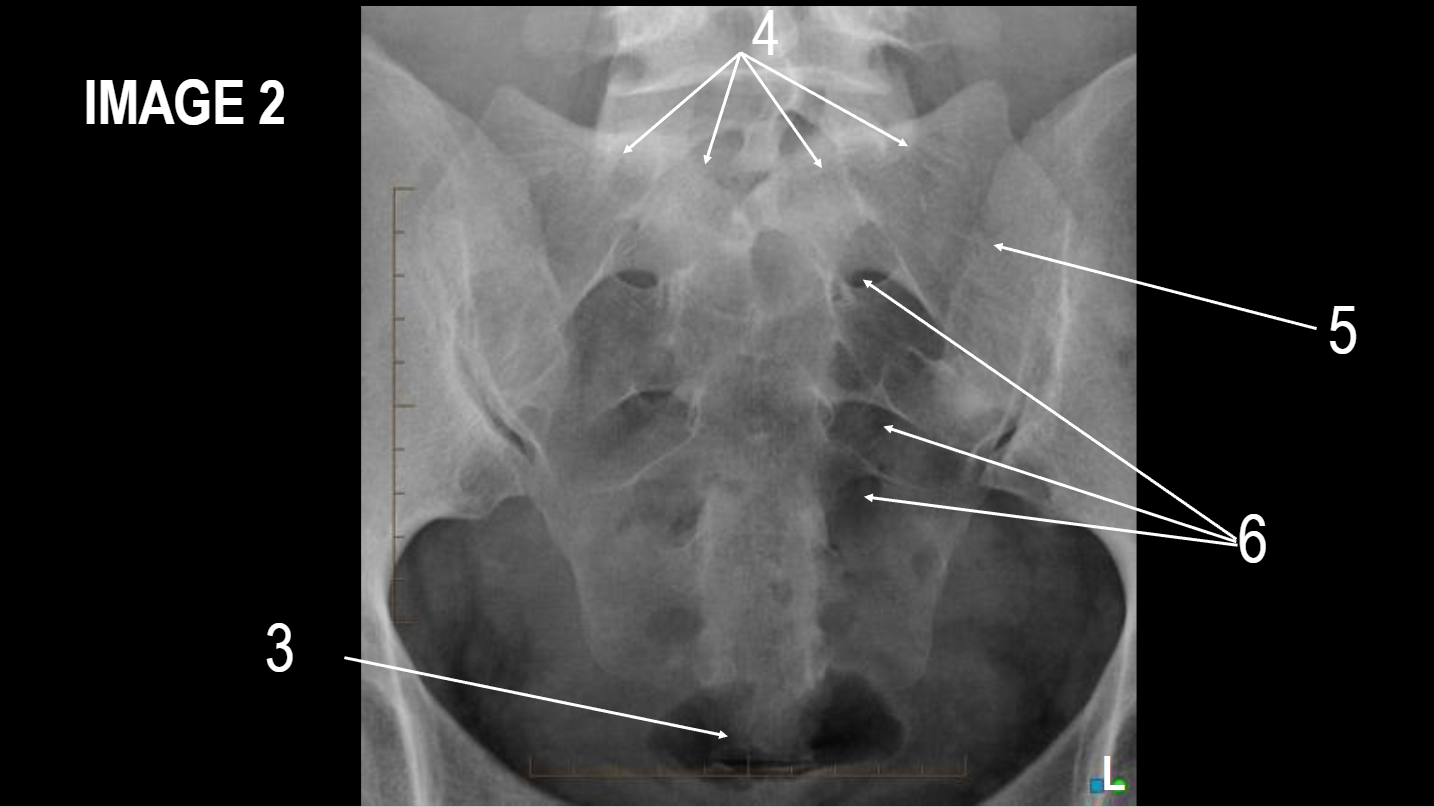

What projection is this

AP Pelvis

A

Right iliac crest

B

Right ala

C

Right ASIS

D

acetabulum

E

right femoral head

F

right femoral neck

G

right greater trochanter

H

right lesser trochanter

I

right ischial tuberosity

J

right obturator foramen

K

inferior ramus of pubis

L

pubic symphysis

M

superior ramus of pubis

N

coccyx

O

left ischial body

P

pelvic brim

Q

ischial spine

R

sacrum